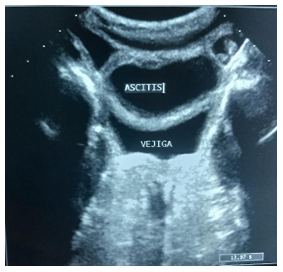

Acude a centro ambulatorio cercano donde solicitan ecografía abdominal con hallazgos de hepatomegalia por lo que refieren a nuestro centro, decidiendo hospitalización bajo tratamiento sintomático con diagnóstico de hepatitis aguda a descartar, se realiza nuevamente ecografía con experto que arroja hepatoesplenomegalia (Figura 2) y bazo midiendo longitudinalmente 13,1 cm con lesiones nodulares mixtas en su interior tipo microabscesos (Figura 3), discreta ascitis sin signos de hipertensión portal (Figura 4). Sin embargo, paciente persiste con ictericia, coluria y acolia, asociándose durante hospitalización epistaxis unilateral y melena en 2 oportunidades más somnolencia, planteándose descartar hepatitis autoinmune, siendo valorada por inmunología quien solicita los siguientes laboratorios: Anticuerpos anti-músculo liso (SMA), anticuerpos antinucleares (ANA) e Inmunoglobulina G (IgG) sérica total, todos resultando negativos. Posteriormente se reciben antígenos febriles (Widal) positivos para S. tiphy O 1/ 20 y S. tiphy H en títulos de 1/40, además de coprocultivo tomado por Instituto Nacional de Higiene Rafael Rangel de Caracas Venezuela positivo para S. typhi grupo H.

Figura 3 Ecografía abdominal. Julio 2025 A y B. Esplenomegalia con medida longitudinal de 13.1 cm, presentando 4 nódulos mixtos heterogéneos sin doppler en su interior C. Esplenomegalia con nódulos, el de mayor diámetro 24 * 22 mm